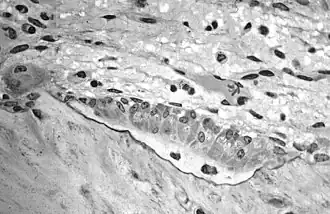

Light micrograph of an osteoclast displaying typical distinguishing characteristics: a large cell with multiple nuclei and a "foamy" cytosol. -

Light micrograph of osteoblasts, several displaying a prominent Golgi apparatus, actively synthesizing osteoid containing two osteocytes. -